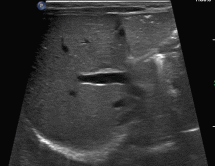

行超声检查,发现一些不一样的声像图表现:

图1~2:腹部探查,见些许点状高回声沿着肠壁朝一定方向快速移动,轨迹如“过山车”一般。